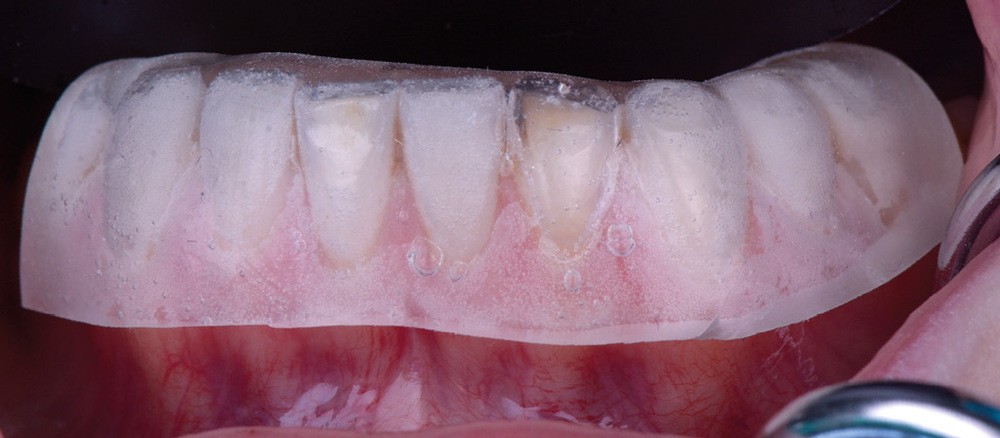

Il existe aujourd’hui sur le marché des résines composites fluides chargées, résistantes mécaniquement et qui présentent de bonnes propriétés optiques. Le choix d’une résine qui présente de bonnes propriétés optiques impose néanmoins une photopolymérisation en fine épaisseur. Ainsi, dans le cas d’une perte de substance supérieure à 2 mm, il est préférable de reconstruire la surface en plusieurs incréments [2]. L’injection de résine au travers de la clé ne concerne ainsi que la couche la plus superficielle.

Afin d’obtenir un comportement optique le plus proche possible de celui de la dent naturelle, l’auteur recommande de réaliser le corps de la dent au préalable à l’aide d’un composite de restauration plus saturé. C’est uniquement la couche la plus superficielle qui est injectée. La technique d’injection de composite nécessite le respect d’un protocole strict et comporte quelques difficultés qu’il convient d’anticiper.

Le wax-up est réalisé au laboratoire par le prothésiste (fig. 2). Il permettra de reproduire l’anatomie de la ou des dents concernées. Il est préférable de ne pas ajouter de cire dans la partie la plus cervicale de la dent afin d’éviter toute fusée de matériau composite lors de l’injection. Par ailleurs, la clé s’appuyant sur la partie gingivale, il est possible de gratter le plâtre d’un dixième de millimètre dans la zone du sulcus et sur la gencive. Cela permet de compenser la dépressibilité des tissus mous (fig. 3).